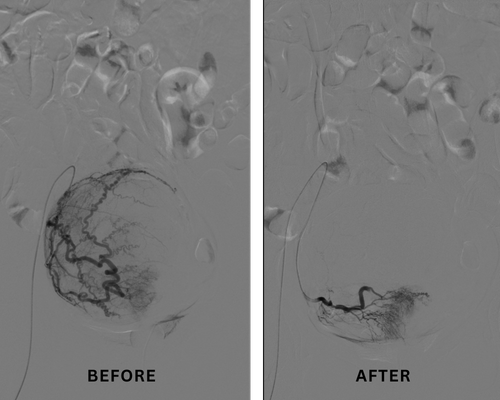

During this procedure, a small needle puncture is made—usually in the wrist or groin—and a thin, flexible catheter is guided under real-time imaging by an Interventional Radiologist to the blood vessels supplying the fibroids. Once the catheter is precisely positioned, tiny embolic particles are injected to block these blood vessels, reducing blood flow to the fibroids. As a result, the fibroids gradually shrink and symptoms improve.

Although fibroid shrinkage occurs over several months, many patients experience relief from symptoms such as heavy menstrual bleeding, pelvic pressure, and pain within days to weeks after UFE, with continued improvement over time.